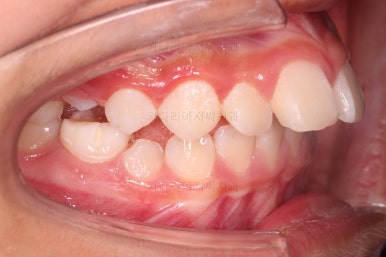

부산소아교정 초진 시 입안의 모습입니다.

윗니가 아랫니보다 많이 앞에 나와있고요.

심지어는 틈새가 벌어지기까지 했습니다.

윗니가 배열 되어있는 U자 형태(그릇 형태)가 아랫니보다 좁은 양상이고요.

이런 앵글씨 2급 부정교합에서는 아랫니가 윗니와 만나기 위해 솟구쳐서 과개교합(아래 앞니가 윗니 뒤쪽으로 깊숙히 올라가 있는 상태)이 나타나기까지 합니다.